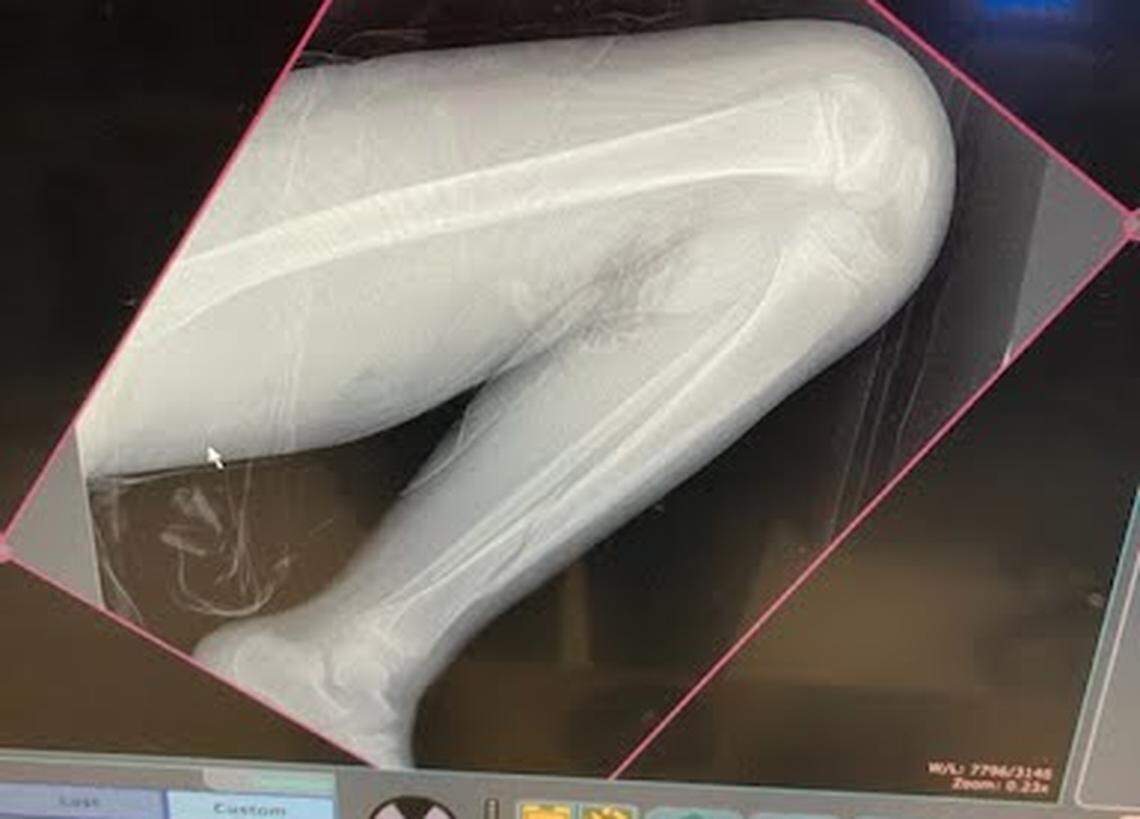

Micah Reed, 8, broke his leg (seen near his ankle) at a North Texas trampoline park.

Micah Reed, 8, broke his leg at a North Texas trampoline park. He was in a full leg cast and temporarily confined to a wheelchair.